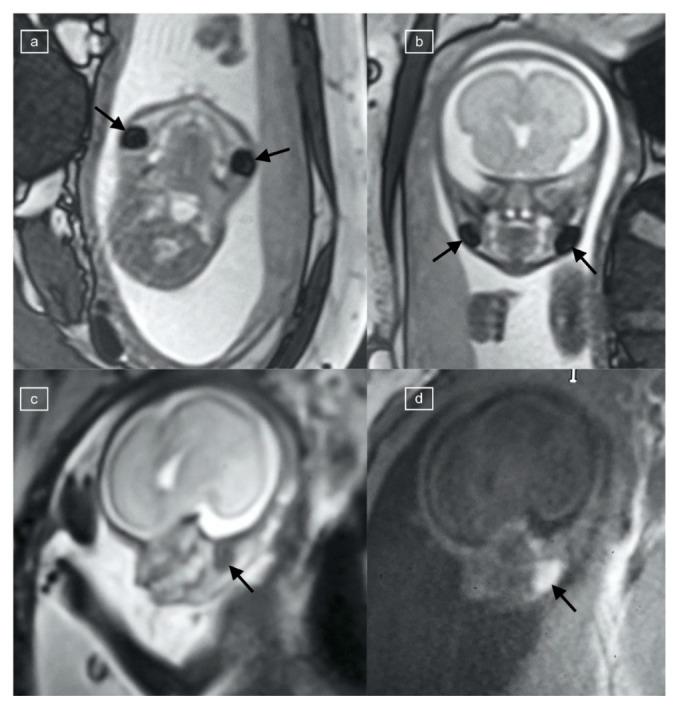

A retrospective review of all fetal MR studies was performed, and a pediatric radiologist blinded to the referring and final fetal diagnosis as well as outcome evaluated the included cases. A positive buccal fat pad sign (BFS) was recorded as present if a round, symmetric, and bilateral area was seen in the submalar region of the face with the following signal characteristics: T1 hyperintensity, low signal on echo planar imaging (EPI), low signal on true fast imaging with steady-state free precession (TRUFI), and with restriction on diffusion-weighted imaging (DWI).

对所有胎儿MR研究进行回顾性分析,由一位对转诊及最终胎儿诊断和结局不知情的儿科放射科医生对纳入病例进行评估。如果在面部颧下区域看到一个圆形、对称且双侧的区域,具有以下信号特征,则记录为存在阳性颊脂垫征(BFS):T1高信号、回波平面成像(EPI)上低信号、稳态自由进动快速成像(TRUFI)上低信号以及扩散加权成像(DWI)上受限。